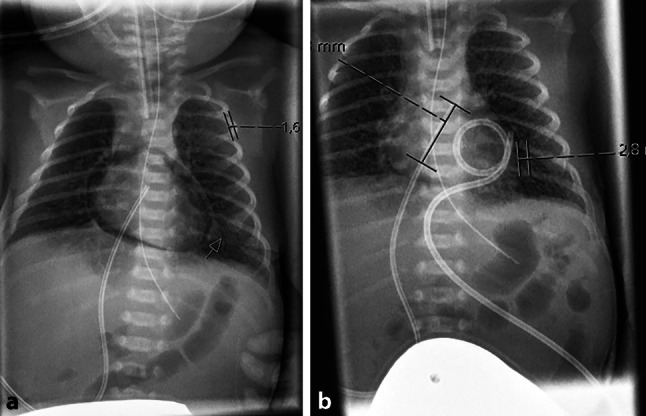

本报告强调了在潜在的心循环损害发生之前,超声心动图对心包积气的早期和异常检测。当常规超声心动图显示心脏出现困难时,在鉴别诊断中考虑心包积气是很重要的。心包积液死亡率高,可通过立即插入心包导管进行有效治疗。

This report highlights the early and unusual detection of a pneumopericardium by echocardiography prior to potential development of cardiocirculatory compromise. It is important to consider pneumopericardium into the differential diagnosis when difficulties arise in the visualization of the heart by conventional echocardiography. Pneumopericardium is associated with a high mortality rate and may be effectively treated by immediate insertion of a pericardial catheter.